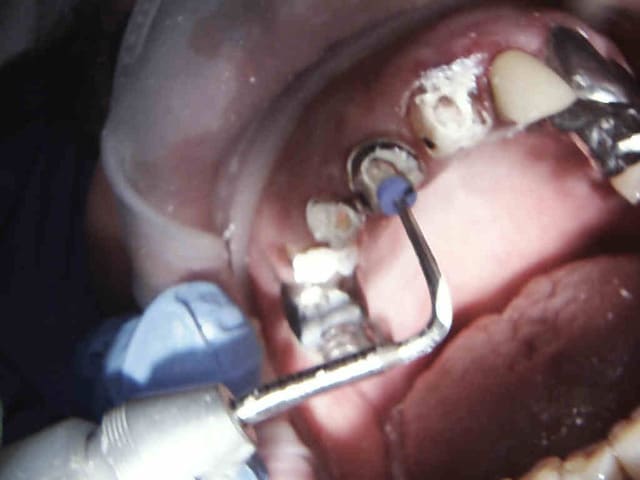

Endo taille empreinte provisoires 2H 30.

Gutta scellée au tubuli seal avec ou sans condensation thermo mécanique.

Logement du tenon réalisé au friendo ( voir photos) qui fond la gutta ( 200 ° au niveau de l'insert) . Un coup de machtou et hop tu peux passer les forets.

Avantage tu peux faire les provisoires et l'empreinte dans la séance et surtout tu peux raser les couronnes ce qui est un réel plus pour les endos surtout avec des pulpes rétractées comme ici ca évite de faire des conneries avec un abord palatin ou on ne voit rien du tout.